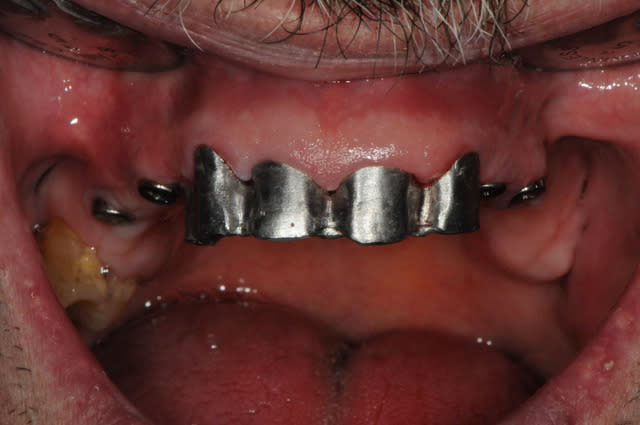

si ça peux alimenter ta réflexion...

manque d'intelligence de ma part j'ai pas fait de photo du cas au tout départ. mais la première photo devrait vous donner une idée du reste...

la suite c'est pose 4 implants, ceramique, stellite sur locators (beaucoup moins couteux qu'une barre et plus facile à nettoyer)

au final, c'est un patient heureux avec un stellite super stable.